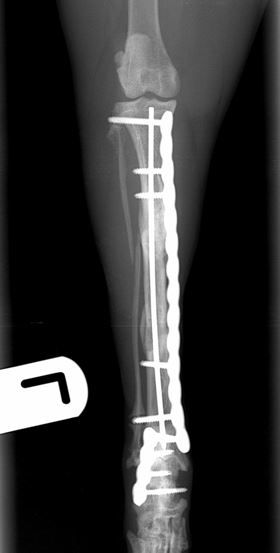

Immediate post-operative radiographs        Immediate post-operative radiographs

Fig. 2 Immediate post-operative radiographs. A 2.4mm PAX plate with an intra-medullary pin has been used to repair the tibial fracture. A 2.0mm PAX plate has been used to repair the comminuted calcaneal fracture